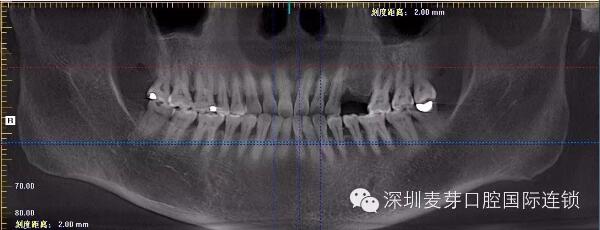

赵女士种植牙前后德国KAVO CT效果对比